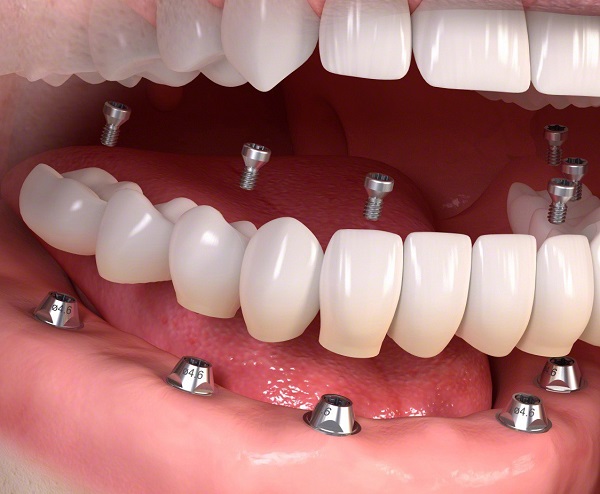

Ngoài ra, tùy vào số lượng răng mất cụ thể mà bác sĩ sẽ đưa ra phương pháp trồng răng Implant phù hợp như trồng răng đơn lẻ, trồng nguyên hàm bằng Implant all on 4 hoặc Implant all on 6. Phương pháp áp dụng phải đáp ứng điều kiện về sức khỏe cũng như tình trạng của người bệnh.